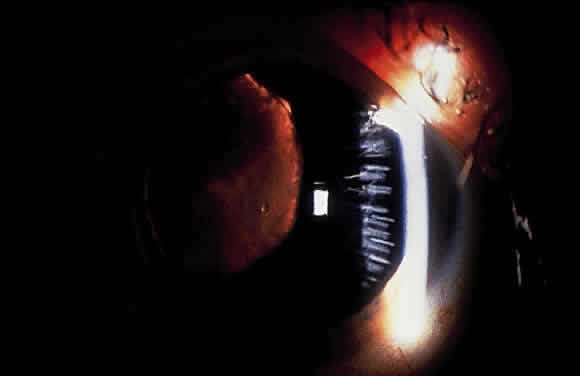

Exfoliation syndrome and pigment dispersion syndrome (PDS) are the two most common causes of increased pigmentation of the trabecular meshwork. The increased trabecular meshwork pigmentation in XFS tends to be less distinct and more patchy than the dense homogeneous deposition of trabecular pigment in PDS43 (Fig. 7). Clinically, the degree of pigmentation in XFS appears to be correlated with the severity of the glaucoma.26,69

Fig. 7. Patchy hyperpigmentation of trabecular meshwork (large arrow) in exfoliation syndrome. Faint pigment on Schwalbe's line represents a Sampaolesi's line (small arrow). Also notice exfoliative deposits in angle. (Van Baskirk EM: Clinical Atlas of Glaucoma, p 53. Philadelphia, WB Saunders, 1986)

Pigment also may be deposited on or anterior to Schwalbe's line (Sampaolesi's line). Occasionally, flakes of exfoliative material may be present in the anterior chamber angle (see Fig. 7). Although the anterior chamber angle usually is open in XFS, acute and chronic angle closure and occludable angles may be seen.9,69–71